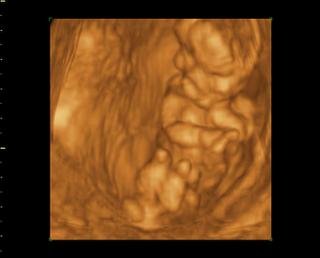

Tak čaute kočky, som doma z 3Dčka, dnes som 14+1 mám plno krásnych fotiek na kľúči, najbližšie mám prísť na 3Dčko v 20tt a potom tretí krát okolo 25 tt a vtedy dostanem aj DVDčko zo všetkých troch UV. Ale fotky aj videá nám dal na USB kľúč takže už teraz mám všetky 🙂 Čo sa pohlavia týka, tak to vyzerá na chlapca, ešte mám aj jednu fotku kde to zreteľne vidieť že to bude asi chlapec. bábo bolo aktívne strašne veľa skákalo a pohybovalo sa, stále si rúčkami chytalo hlavičku (to robí aj Danko stále 😀 ) Priateľ bol vnútri so mnou takže to celé videl.